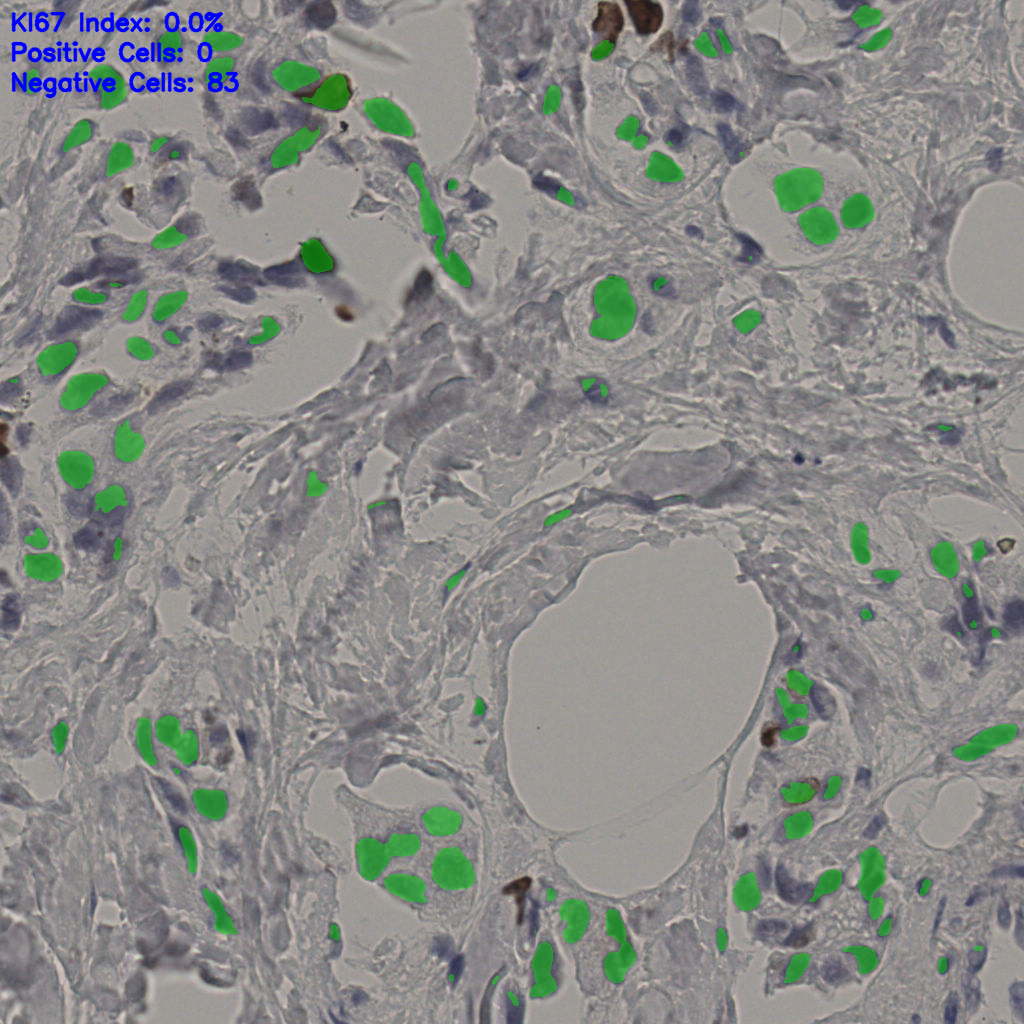

Ki67 指数

阴 19502 阳 1093

5.31%